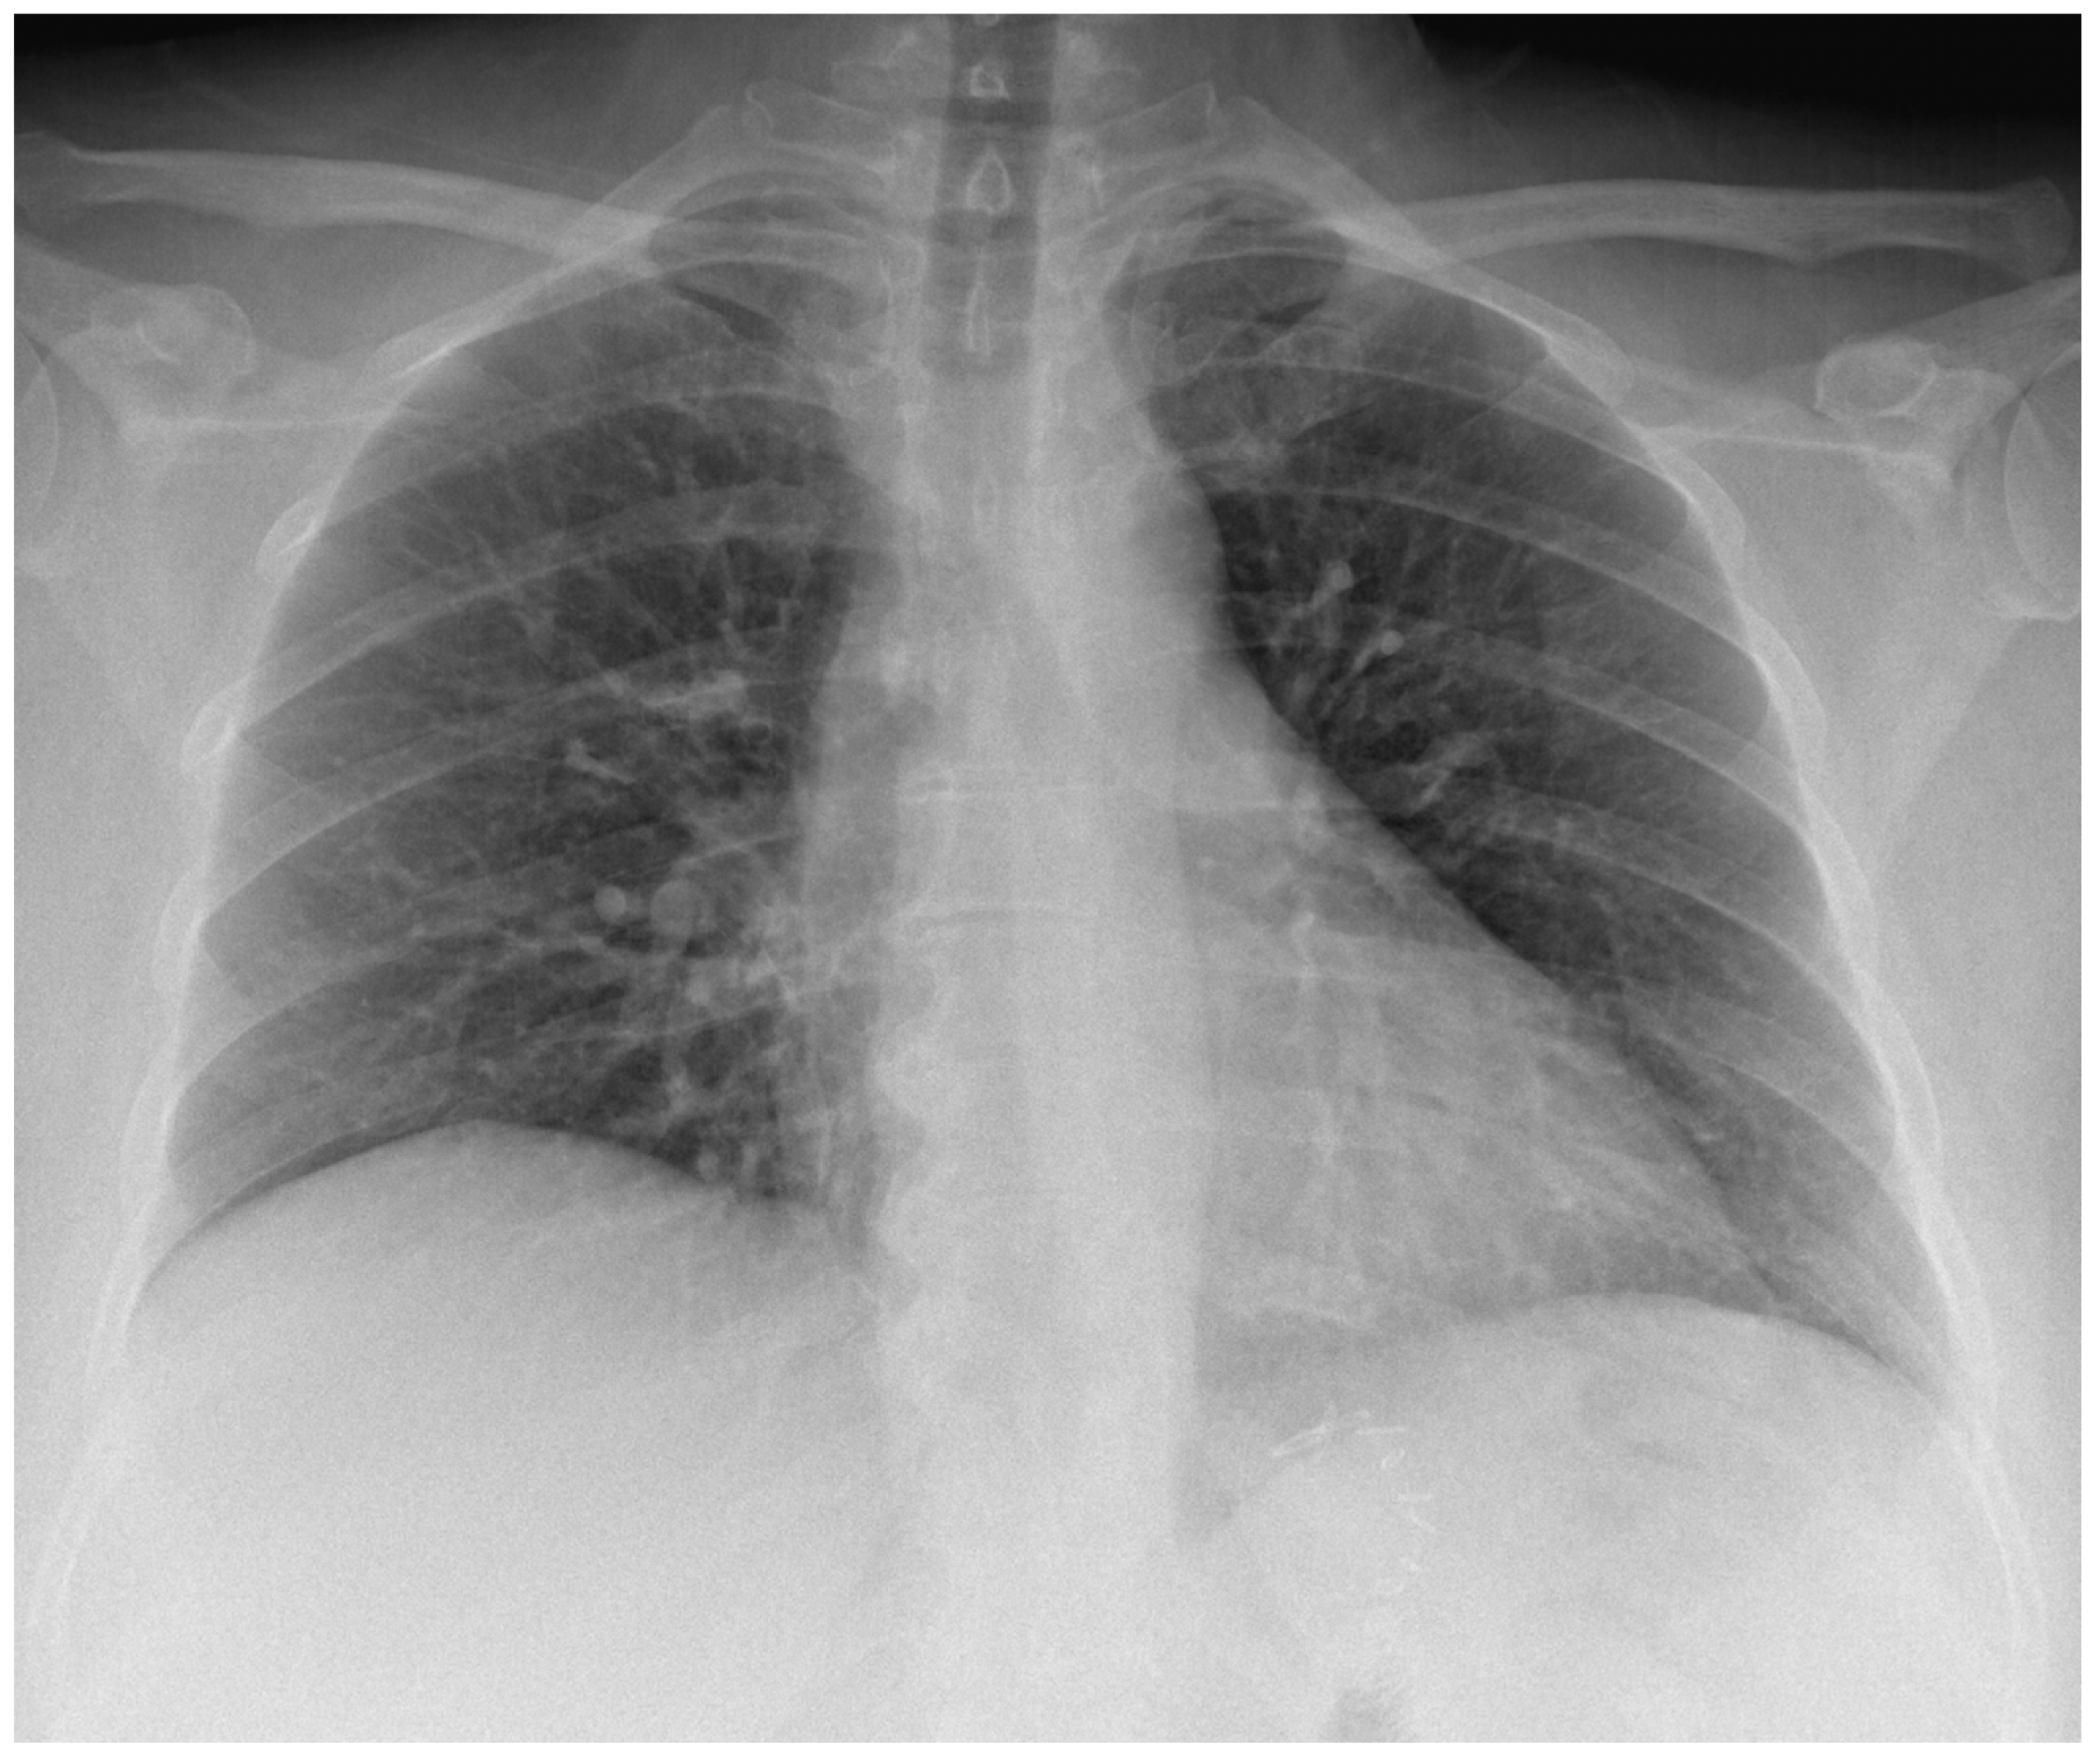

The chest radiography showed clear lungs and pleural spaces and regular cardio mediastinal counter (Figure 4), thus excluding tuberculosis and, implicitly, Pott’s disease and tuberculous spondylitis as causes of iliopsoas abscess. Despite a thorough CT scan examination, no evidence of colonic micro-perforations was found, leaving the cause uncertain. Additionally, the patient explicitly denied any past involvement in intravenous drug abuse. Furthermore, we requested an evaluation of the patient by the general surgeon on call, who recommended emergency hospitalization and surgical drainage, so she was transferred to the general surgery department.

Figure 4.

The chest radiography was performed in the ED.